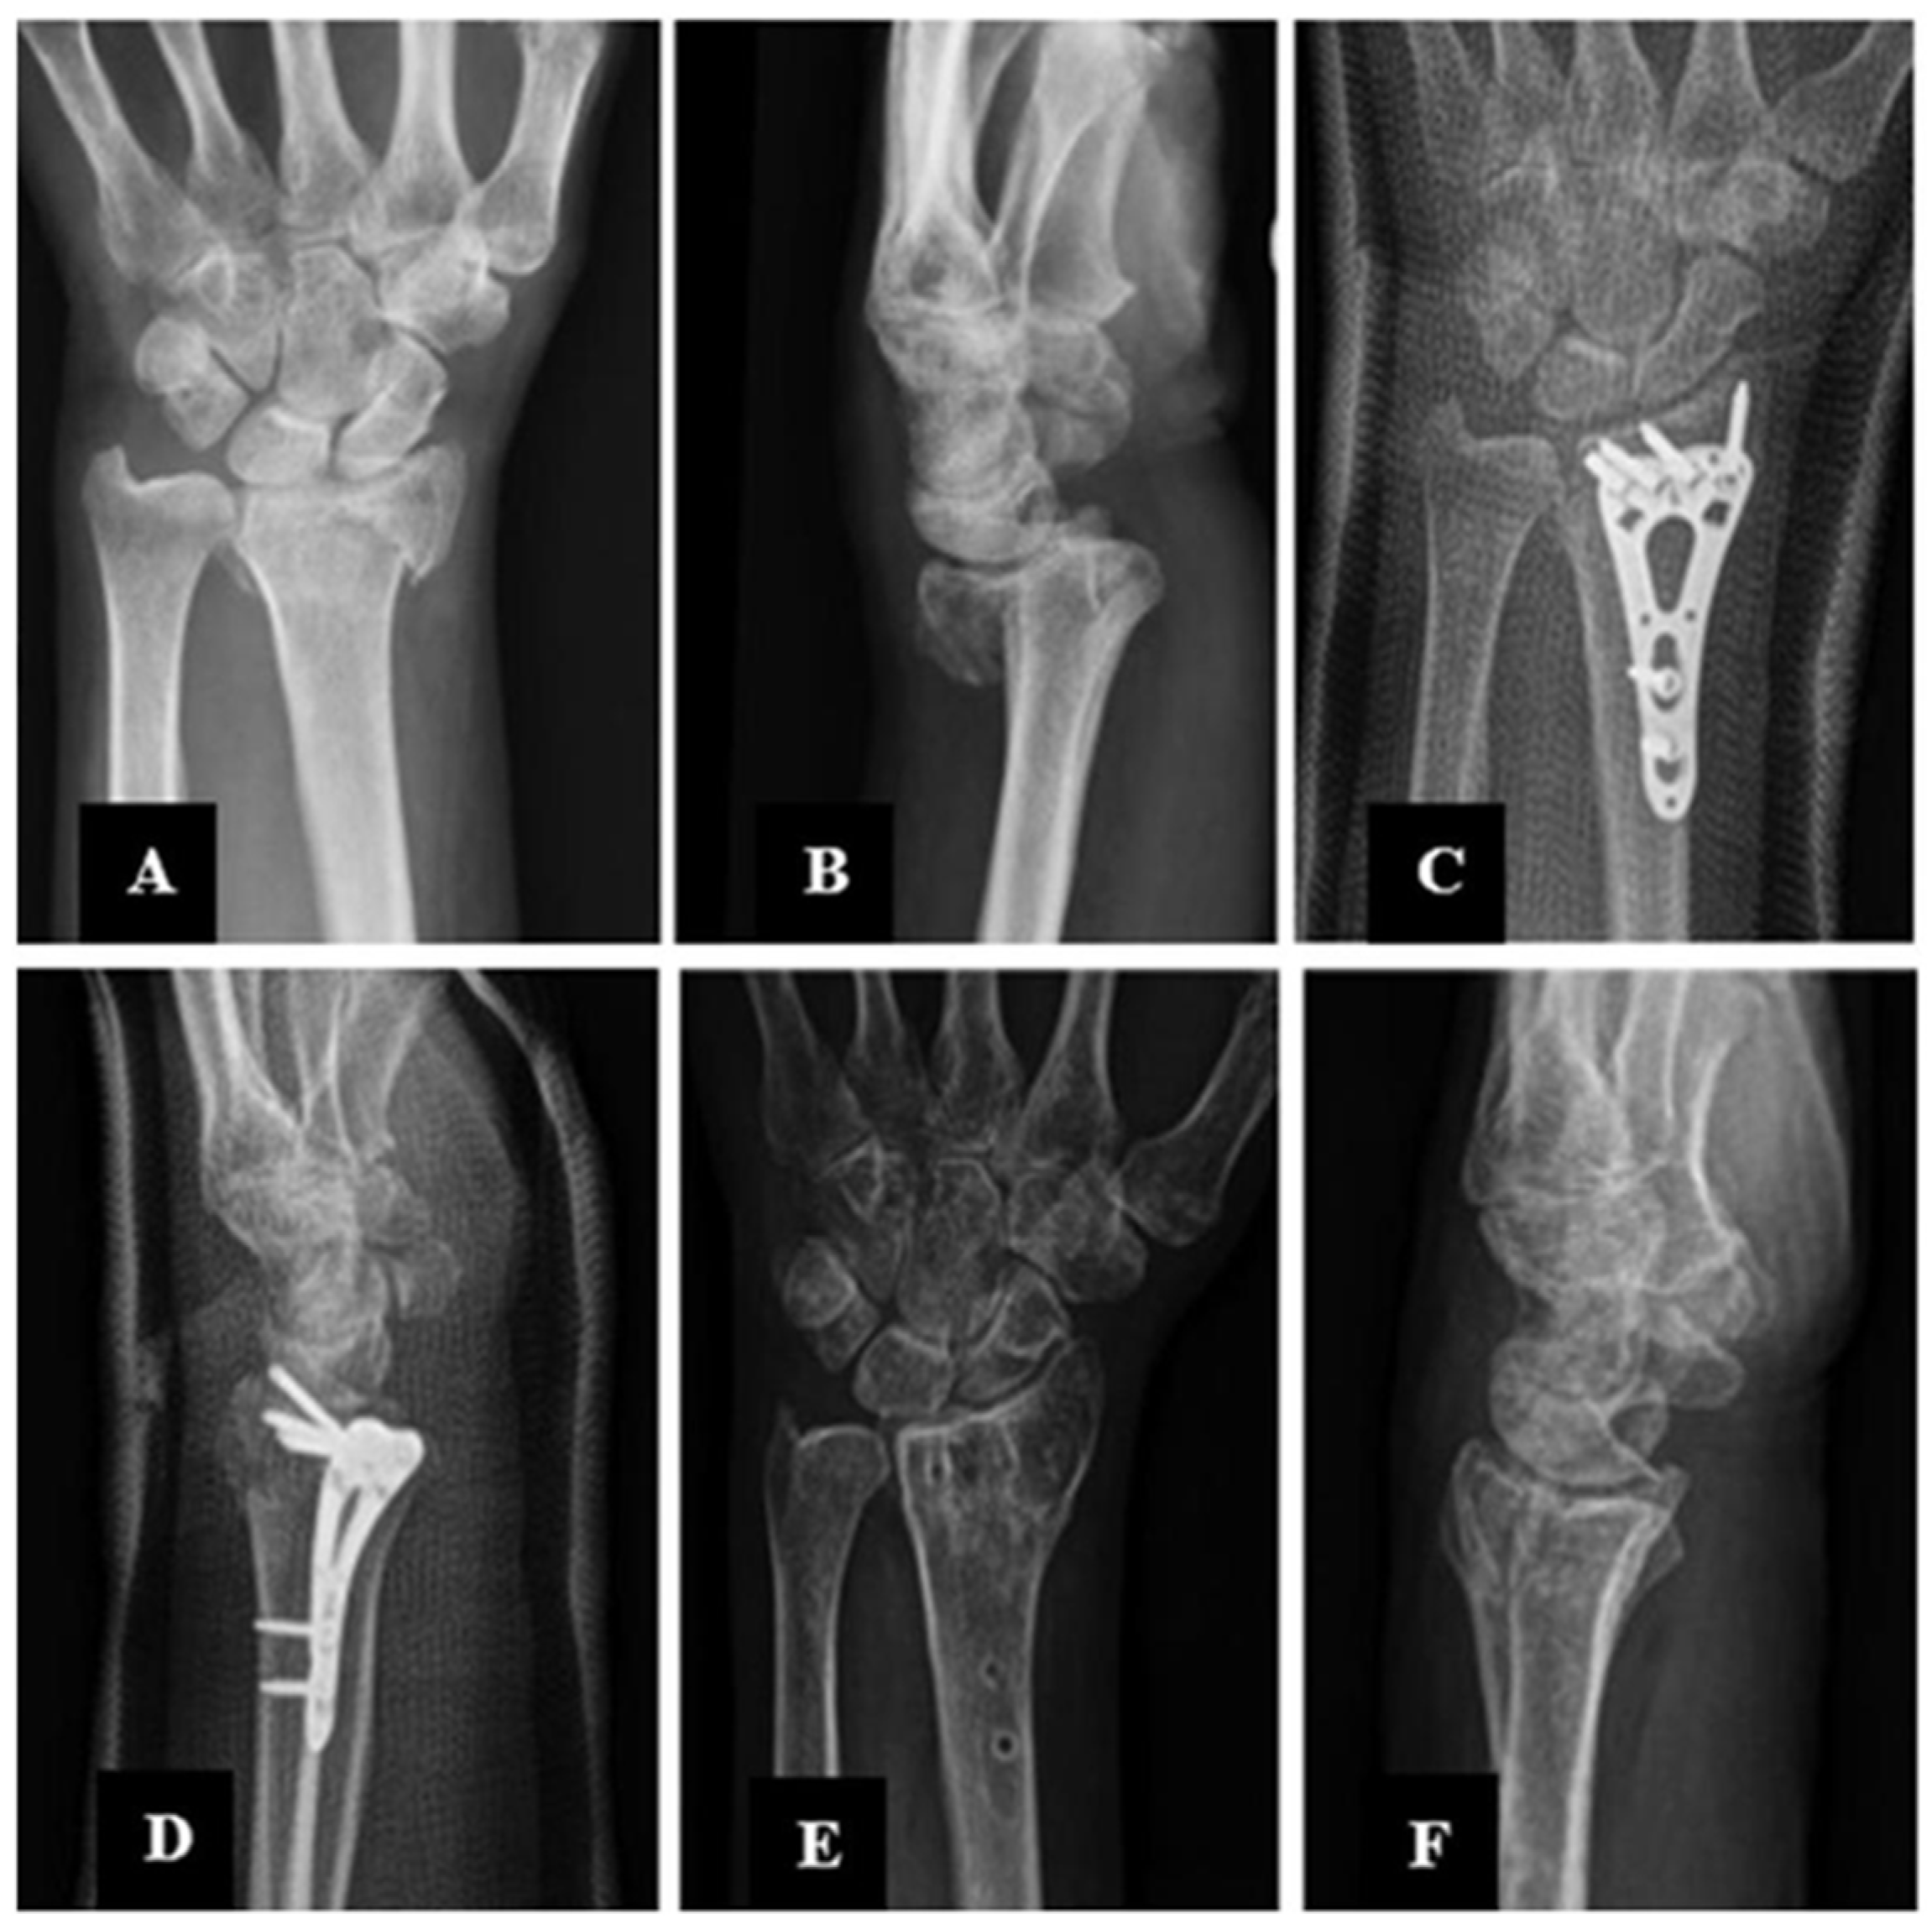

Surgical Treatment of Distal Radius Fractures Using Minimally Invasive Plate Osteosynthesis or Open Reduction and Internal Fixation: A Five-Year Comparative Follow-Up Study

2. Materials and Methods

2.3. Description of the Experimental Stage